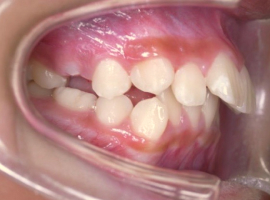

側面

- Before